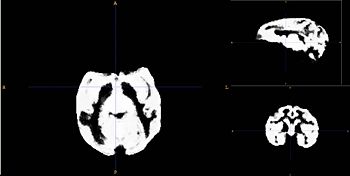

| − | Image:T1template_Cr.jpg|Population Specific T1 template image | + | Image:T1template_Cr.jpg|Population Specific T1 template image|left |

- Using a rhesus tissue atlas provided by the UNC Neuro Image Analysis Laboratory and the UWisc Harlow Primate Laboratory we have segmented the data into WM/GM, and CSF capartments using the Lobulated EM Segmentation method. These segmentations have been averaged to create a study-specific tissue atlas.

- Rhesus Probabilistic Atlas